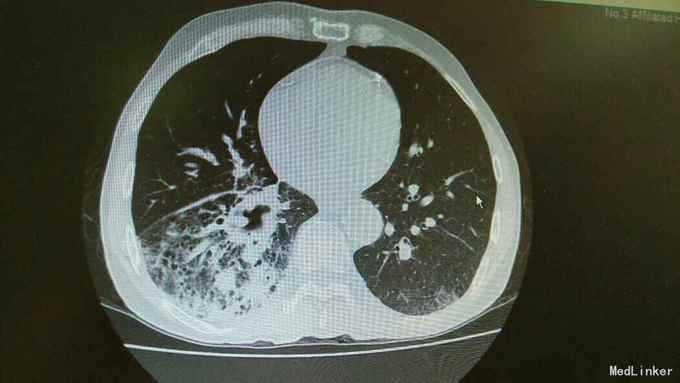

主诉:活动后气促,胸闷1年,消瘦8月余。 病史:患者1年前无明显诱因出现活动后气促,胸闷,主要为胸骨段,爬坡可诱发,伴有咳嗽,白色粘痰。伴有体重下降。

查体:慢性病容,桶状胸,双肺呼吸音粗,右下肺可闻及少量细湿罗音。 辅查:胸部CT:考虑右下肺中央型肺癌并癌性空洞形成,右下肺阻塞性肺炎 ,右下肺动静脉受累,纵隔,双侧肺门多发淋巴结肿大。

诊断:中央型肺癌并阻塞性肺炎。 治疗:入院予以抗感染,止咳化痰等治疗。